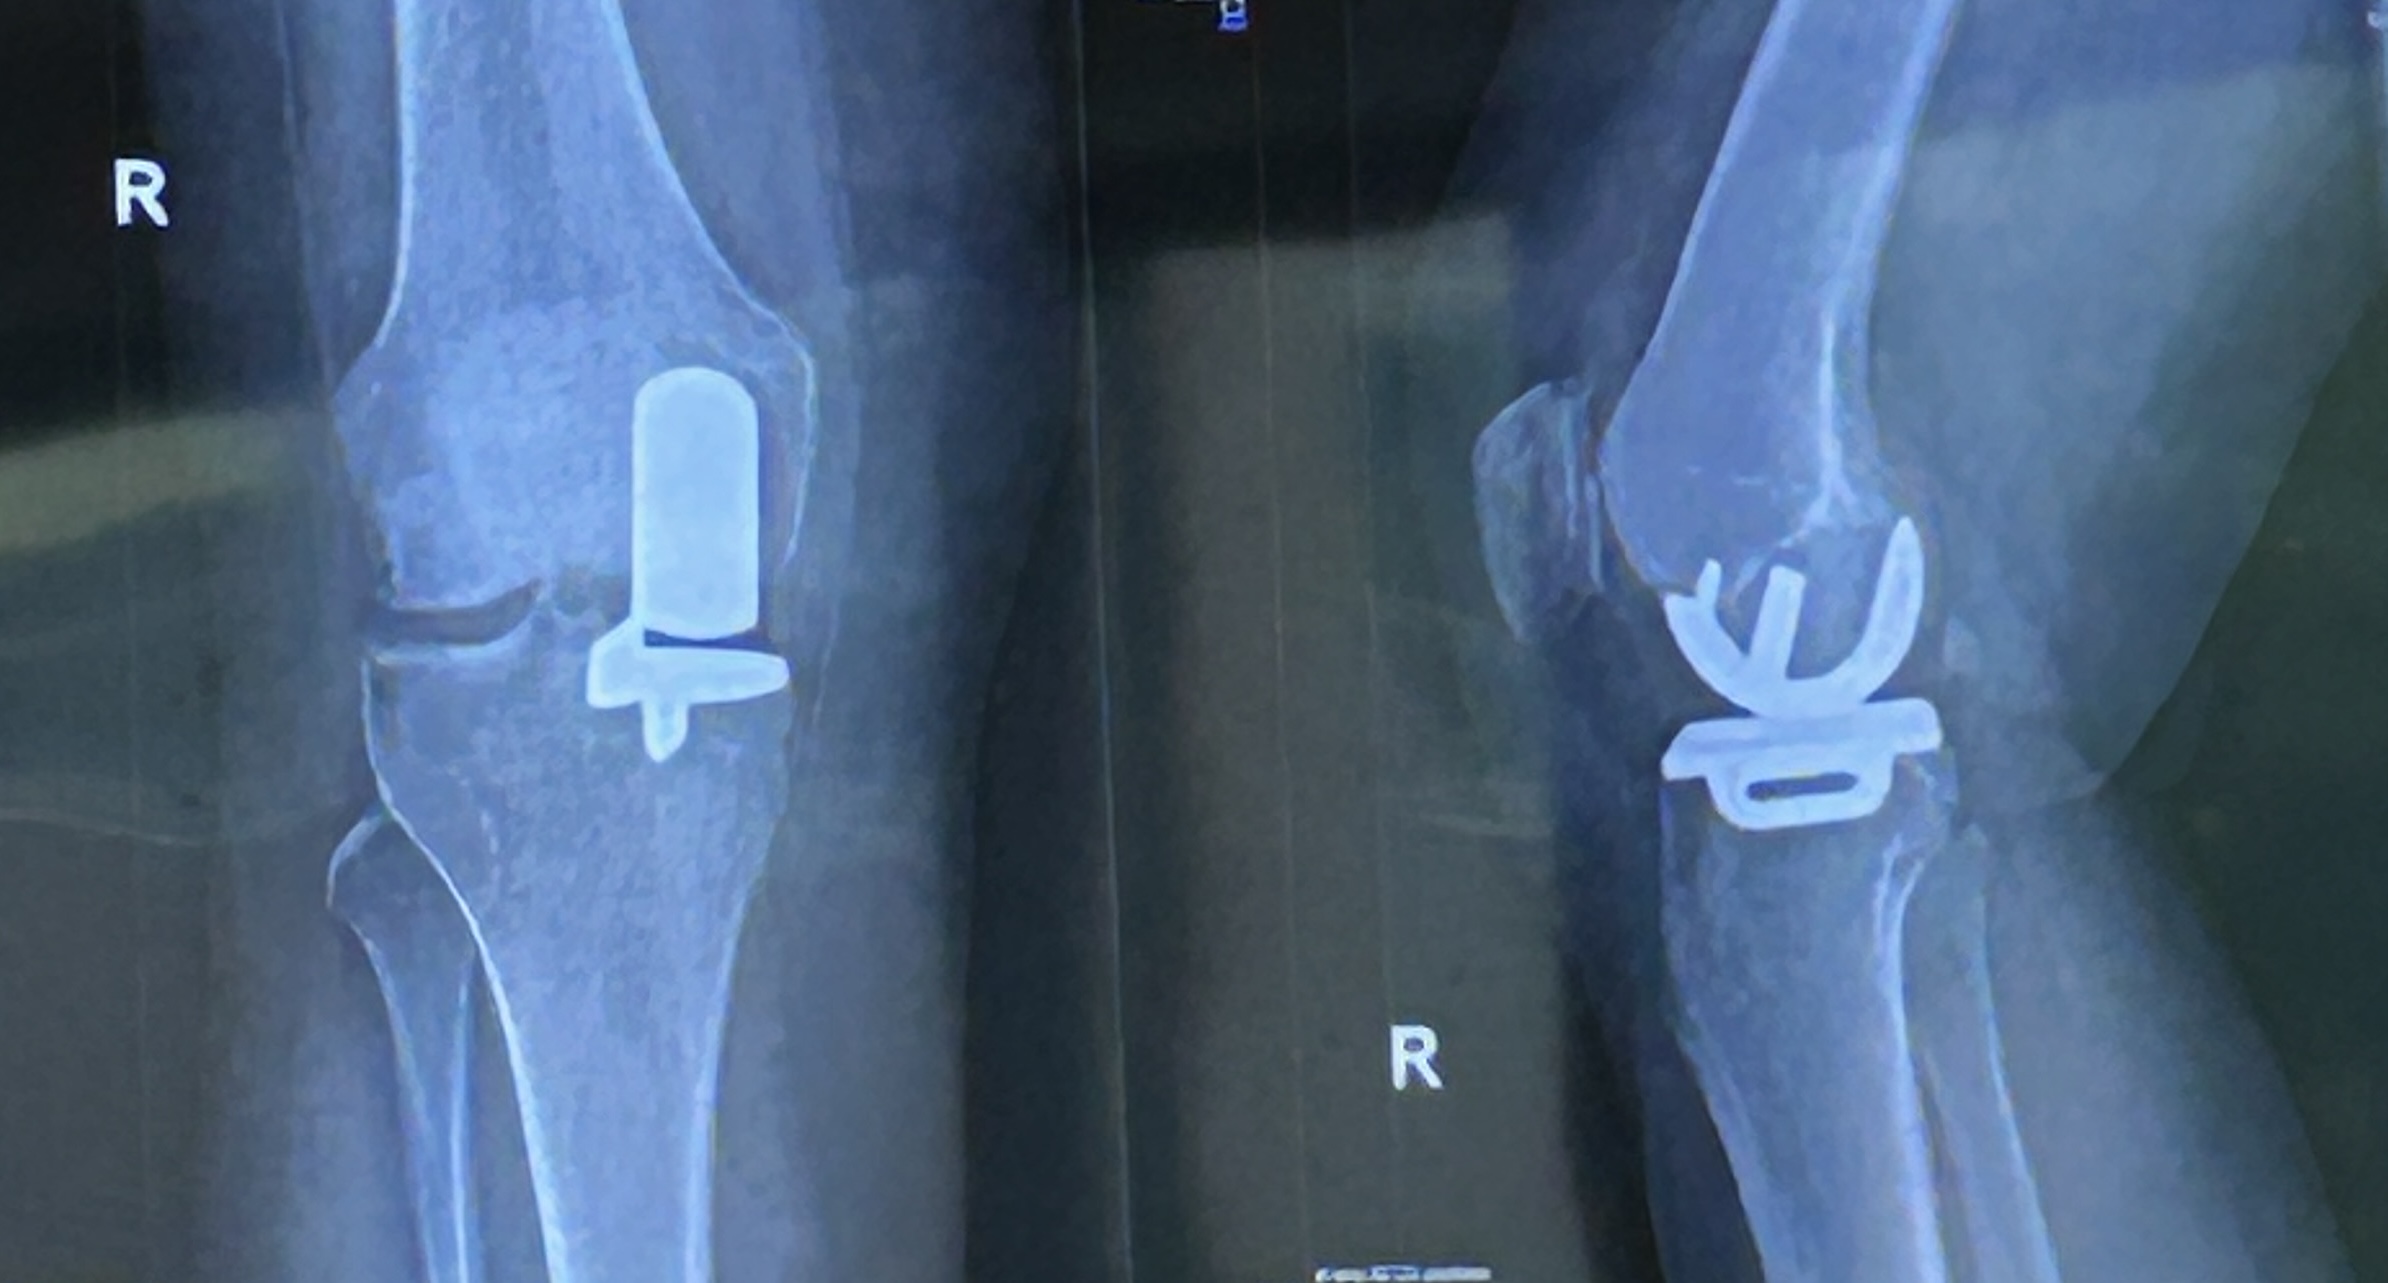

Revalidatie: Het is inmiddels 8 weken geleden dat Joyce een nieuwe (halve) knie heeft gekregen. Het herstel valt nog niet mee. Aan de buitenkant herinnert een klein streepje nog aan de operatie. Op een paar meter afstand valt het bijna niet meer op. Van binnen loopt het echter nog niet gesmeerd. Wij bezochten deze week een afsluitende lotgenoten bijeenkomst. Een groep van zo’n 12 mensen die een nieuwe (hele of halve) knie had gekregen. Net voor de operatie kwamen ze ook bij elkaar. Een arts en een orthopeed bespraken de kort daarvoor genomen röntgenfoto’s en de vorderingen van een ieder werden getest. Bij de één was het gewricht weer soepel als voorheen (iemand rende zelfs alweer) en bij de anderen was het buigen en strekken in allerlei gradaties aanwezig. Joyce bleek de ‘slechtste’ van de klas te zijn en ja, dan moet je nablijven. De arts en de orthopeed bekeken de knie nog eens en kwamen met een dringend advies: “Ga met buig-oefeningen door de pijngrens om daarmee het binnenkapsel van de spieren te laten scheuren. Je merkt zelf dat dit gebeurt en dat voel je, maar het kan geen kwaad. (Oeps!!!) Voor het doorbuigen naar de andere kant leg je je been op een stoel met 3 kilo zand op je knie. Ook dat ga je na een minuut of vijf flink voelen. Half uurtje volhouden. (!!!) En op de hometrainer net zo lang heen en weer trappen tot je rond gaat. De tranen springen je bij dit alles ongetwijfeld in de ogen, maar daarna merk je pas hoe fijn het is om een nieuwe knie te hebben. (Ja, ja, dat is pas vreugde). O ja, je moet wel extra sterke pijnstillers en een maagbeschermer slikken. Blijft angst jouw pijngrens bepalen, dan brengen wij je onder narcose en gaan de knie zelf doorbuigen. Dan scheurt het kapsel pas echt goed, maar dat merk je pas wanneer je uit narcose komt. Dat wil je natuurlijk niet, dus ga aan de slag. Doen jij of wij verder iets, dan verhardt het spierkapsel en blijft de knie de rest van je leven stijf” . Zoooo…dat is een pittig en streng advies! In de films van ‘The Godfather’ noemen ze dat zo ongeveer ‘An offer you can’t refuse’. Er klonken nog een paar ‘Ja maren…’ uit Joyce haar mond, maar dat veranderde niks aan het advies. Dus is er meteen een hometrainer aangeschaft en heb ik zes zakjes met elk een pond aan gewicht aangemaakt. Voor de overige oefeningen waren er voldoende trappetjes en hekjes voor een Squat-oefening in ons huis aanwezig. Joyce werkt inmiddels een paar dagen hard aan de ‘verscheurende kapsel’ oefeningen. Er klinken heel wat ‘Auws’ en ‘Aahs’ en er is veel napijn, maar er is wel vooruitgang. De buighoek is nu 90 graden, maar moet nog naar 110 graden.